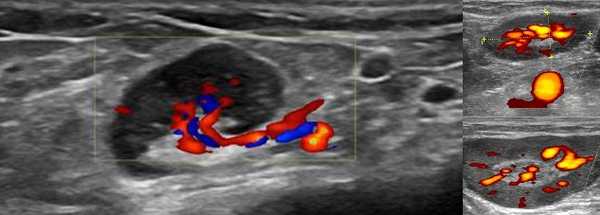

УЗИ с допплерографией у пациентов онкологического профиля показывает следующие нарушения в строении ЛУ:

- увеличение в размерах - обычно до 6-6,5 см;

- шарообразную деформацию или неправильные контуры;

- спаянность в виде конгломератов;

- отсутствие дифференциации на кору и ворота;

- неоднородность структуры с зонами повышенной и пониженной эхогенности;

- жидкостные включения и кальцинаты;

- усиленный кровоток и образование новых сосудов (ангиогенез).

Указанные изменения на снимках чаще обнаруживают при лимфоме.